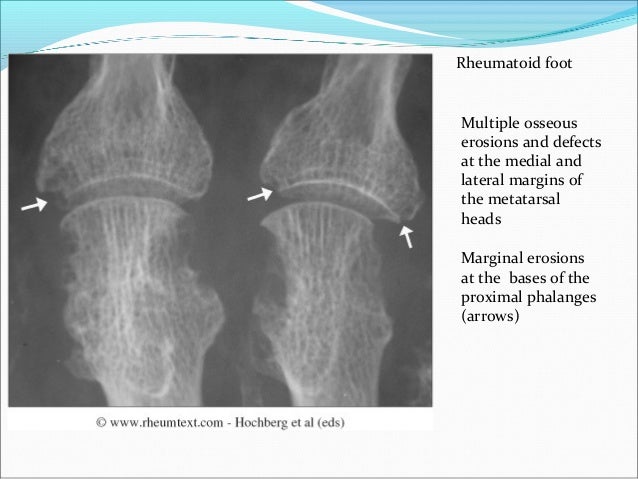

Avascular Necrosis Of The Femoral Heads - X Rays Case Studies - CTisus

necrosis avascular femoral ct ctisus rays diagnosis studies case